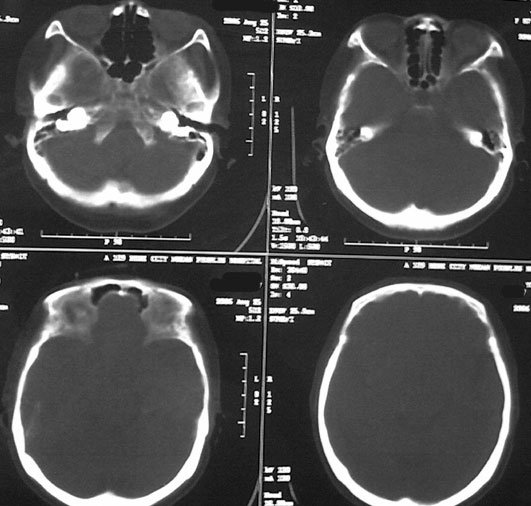

女87左下肢麻木,无外伤史

右侧大脑半球脑沟 脑裂变浅或消失,顶叶不规则低密度影,右侧侧脑室明显受压移位,中线偏移,右侧内板下新月形混杂高密度致密影,多考虑:慢性硬膜下血肿.必要时建议强化扫描.

右额颞顶部颅骨内板下方新月形混杂密度影,同侧灰白界限受压内移,右侧脑室呈受压性改变,中线结构左移;应该是右额颞顶部慢性硬膜下血肿,建议mri检查。

左顶叶片状低密度影,应是局限扩大的蛛网膜下腔。

右侧脑室前角受压变小,中线左移,考虑慢性硬膜下血肿.左侧脑软化灶.

右侧颞顶颅内板下可见新月状高低混杂密度影,右侧脑沟回消失,脑组织受压中线结构左移,考虑为右侧慢性硬膜下血肿。病人情况允许可做mri检查。我们遇到过几例没外伤史的病人有硬膜下出血的,多为六七十岁的老年患者,不知慢性硬膜下血肿与年龄有关否?